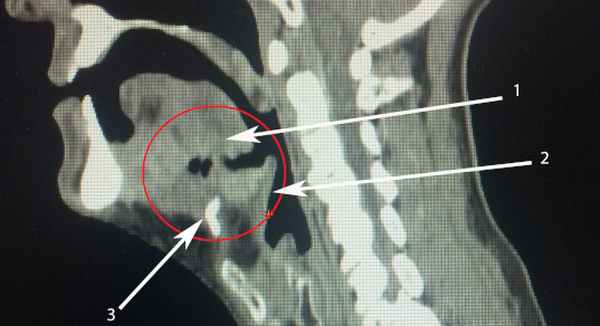

- Методы лучевой диагностики.Рентгенография шеи дает возможность определить круглую или овальную полостную, заполненную воздухом структуру с четкими границами в области проекции желудочков гортани. Она может распространяться до подъязычной кости, деформируя черпалонадгортанную складку. КТ шеи или МРТ мягких тканей шеи назначаются при невозможности четкой дифференциации с другими патологиями.